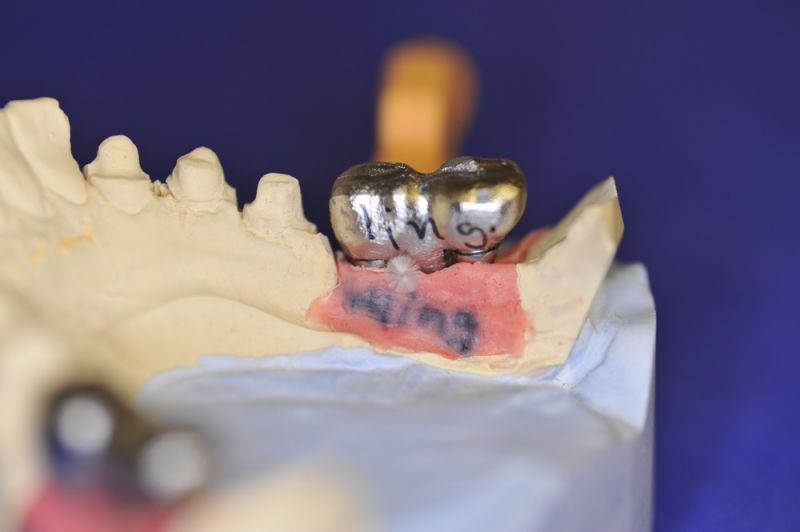

Es war eine Kombination aus Schmerzen bis an die Suizidgrenze, beschränkten wirtschaftlichen Möglichkeiten, sehr stark eingeschränkten Möglichkeiten der für Implantate zur Verfügung stehenden Knochenverhältnisse in einem stark atrophierten Unterkieferseitenzahnbereich und zudem dann auch noch durch auftretenden Problemen bei der Implantatinsertion und nachfolgenden Versorgung der Implantate.

Die Problematik der Implantatversorgungen kann man in einer Analogie folgendermaßen darstellen. Die räumlich beengten Zustände gleichen dem Tanz eines Paares auf einer Briefmarke, und der gleichzeitigen Schritt- und Fusshaltung, dass beim Tanzen die Schuhe geputzt werden können!